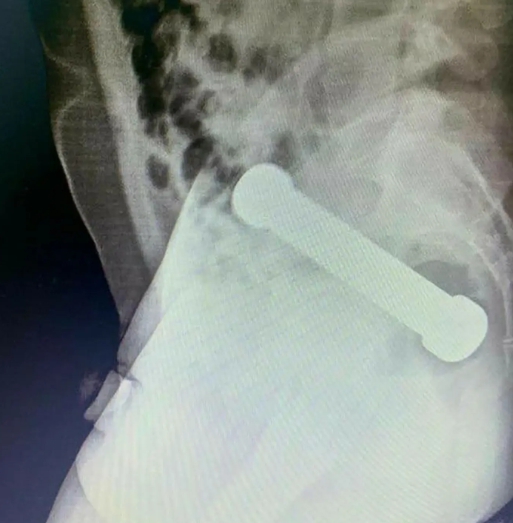

Po vyšetrení röntgenom bolo jasné, že predmet je uviaznutý na spojení hrubého čreva a konečníka a predstavuje riziko perforácie alebo iného vážneho poranenia. Najprv sa lekári pokúsili predmet odstrániť pinzetou, čo sa nepodarilo, a nakoniec musel chirurg zasiahnuť manuálne – do konečníka zasunul ruku až po predlaktie, aby činku bezpečne vytiahol.